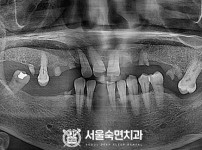

상악동거상술, 뼈이식 / 숙면임플란트 11개 - 포인트임플란트 (이*정님)

해당 게시물은 의료법 제56조에 의거하여 로그인 후 열람이 가능합니다.

구분 임플란트